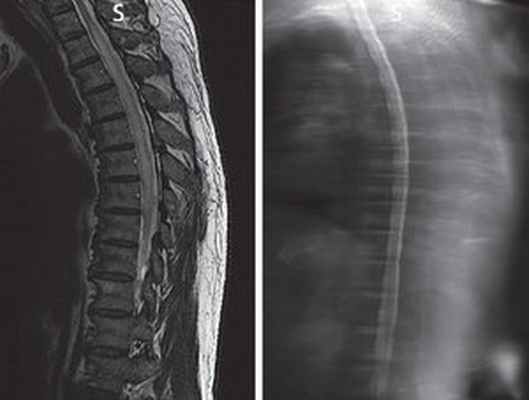

МРТ при паранеопластической миелопатии

Миелит — воспалительное заболевание СМ, захватывающее часть его поперечника с поражением как серого, так и белого вещества. Этиология заболевания может быть различной: вирусный, параинфекционный, токсический, паранеопластический процесс, а также миелит при системных аутоиммунных процессах. В большинстве случаев при изолированном воспалении СМ причину заболевания выяснить не удается. К категориям поперечного миелита относят: острый парциальный поперечный миелит и острый полный поперечный миелит, продольный распространенный поперечный миелит. Острый парциальный поперечный миелит характеризуется асимметричным поражением СМ, не превышающим трех сегментов. Острый полный поперечный миелит сопровождается полным/почти полным неврологическим дефицитом ниже уровня повреждения СМ протяженностью не более трех сегментов. «Продольно распространенный поперечный миелит» (LETM — Longitudinally Extensive Transverse Myelitis) — относительно новый термин, под которым понимают идиопатический поперечный миелит. Наиболее частой формой LETM является оптиконейромиелит, при котором спинальные очаги характеризуются центральной локализацией, склонностью к слиянию и увеличением протяженности более чем на три сегмента в длину и более чем на 50 % площади поперечного среза [8]. Наиболее частая локализация подобного миелита — грудной отдел СМ. Доминируют двигательные спинальные нарушения: прогрессирующая спастическая параплегия сменяется вялым параличом в восходящем направлении. Расстройства чувствительности только вначале заболевания имеют диссоциированный, а затем приобретают тотальный характер. Они сопровождаются нарушениями функции тазовых органов (НФТО). Прогрессирование симптомов наблюдается в течение 2 недель. Со стороны ЦСЖ отмечается белково-клеточная диссоциация с легким/умеренным плеоцитозом. При нейровизуализации (магнитно-резонансная томография — МРТ) обнаруживается асимметричное или симметричное поражение трех или более спинальных сегментов СМ (при продольном распространенном миелите). Одним из наиболее важных диагностических тестов при оптиконейромиелите, чувствительность которого составляет 50–75 %, а специфичность — 90 %, является определение в крови антител к аквапорину-4 [5, 8].

Частота интрамедуллярных опухолей среди пациентов всех возрастов составляет 10–18 % от общего числа опухолей СМ [8]. Боль в спине не столь типична. Опухоль, как правило, поражает несколько спинальных сегментов. Клиническая картина таких опухолей СМ развивается достаточно медленно, и на первое место выходят прогрессирующие двигательные расстройства, а чувствительные нарушения, согласно закону эксцентрического расположения длинных проводников, распространяются сверху вниз [17]. В случае кровоизлияния или инфаркта в опухоль симптомы могут развиться остро и имитировать острый поперечный миелит. МРТ регистрирует очаг, захватывающий несколько сегментов СМ, изо- или слабогипоинтенсивный в Т1-взвешенном изображении (ВИ), с неоднородным усилением сигнала от очага в Т2-ВИ. Типичны перифокальный отек, инфильтративный рост, увеличение в размерах СМ, чаще с неровными бугристыми краями. При введении контрастного вещества типично персистирующее накопление контраста, сохраняюще–еся месяцами, несмотря на лечение [7, 23]. Интрамедуллярные метастазы встречаются крайне редко, у 1–2 % больных с раком легких, молочной железы, почки, при меланоме [2]. Боль в спине чаще всего служит первым, хотя и не обязательным симптомом интрамедуллярного метастаза, вслед за ней развиваются нарастающий спастический парапарез и парестезии. Диссоциированное расстройство чувствительности наблюдается редко, обычно отмечаются асимметричный парапарез и частичная утрата чувствительности. При миелографии, компьютерной томографии (КТ) и МРT выявляется отечный СМ без признаков внешней компрессии; почти у 50 % пациентов КТ и миелография показывают нормальную картину.